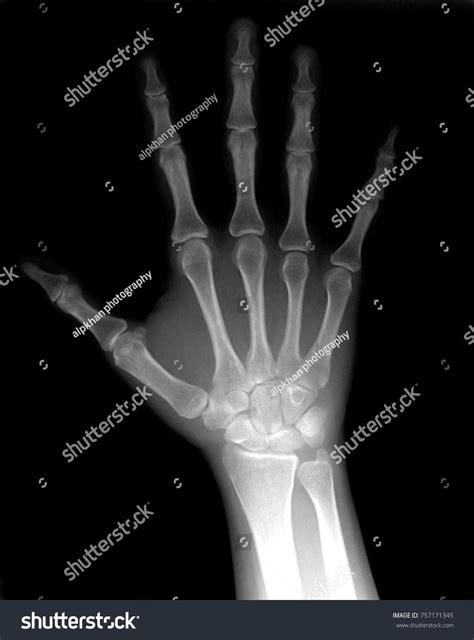

A broken hand x-ray is a type of medical imaging that uses low levels of radiation to produce images of the bones in the hand. These images are crucial for diagnosing fractures, dislocations, and other bone-related injuries. The x-ray machine emits X-rays that pass through the body and are absorbed differently by various tissues. Bones, being denser, absorb more X-rays and appear white on the resulting image, while softer tissues appear darker.

Interpreting the results of a broken hand x-ray requires a trained eye. Here are some key points that healthcare professionals look for:

• Fracture Lines: These appear as thin, white lines on the x-ray image and indicate a break in the bone.